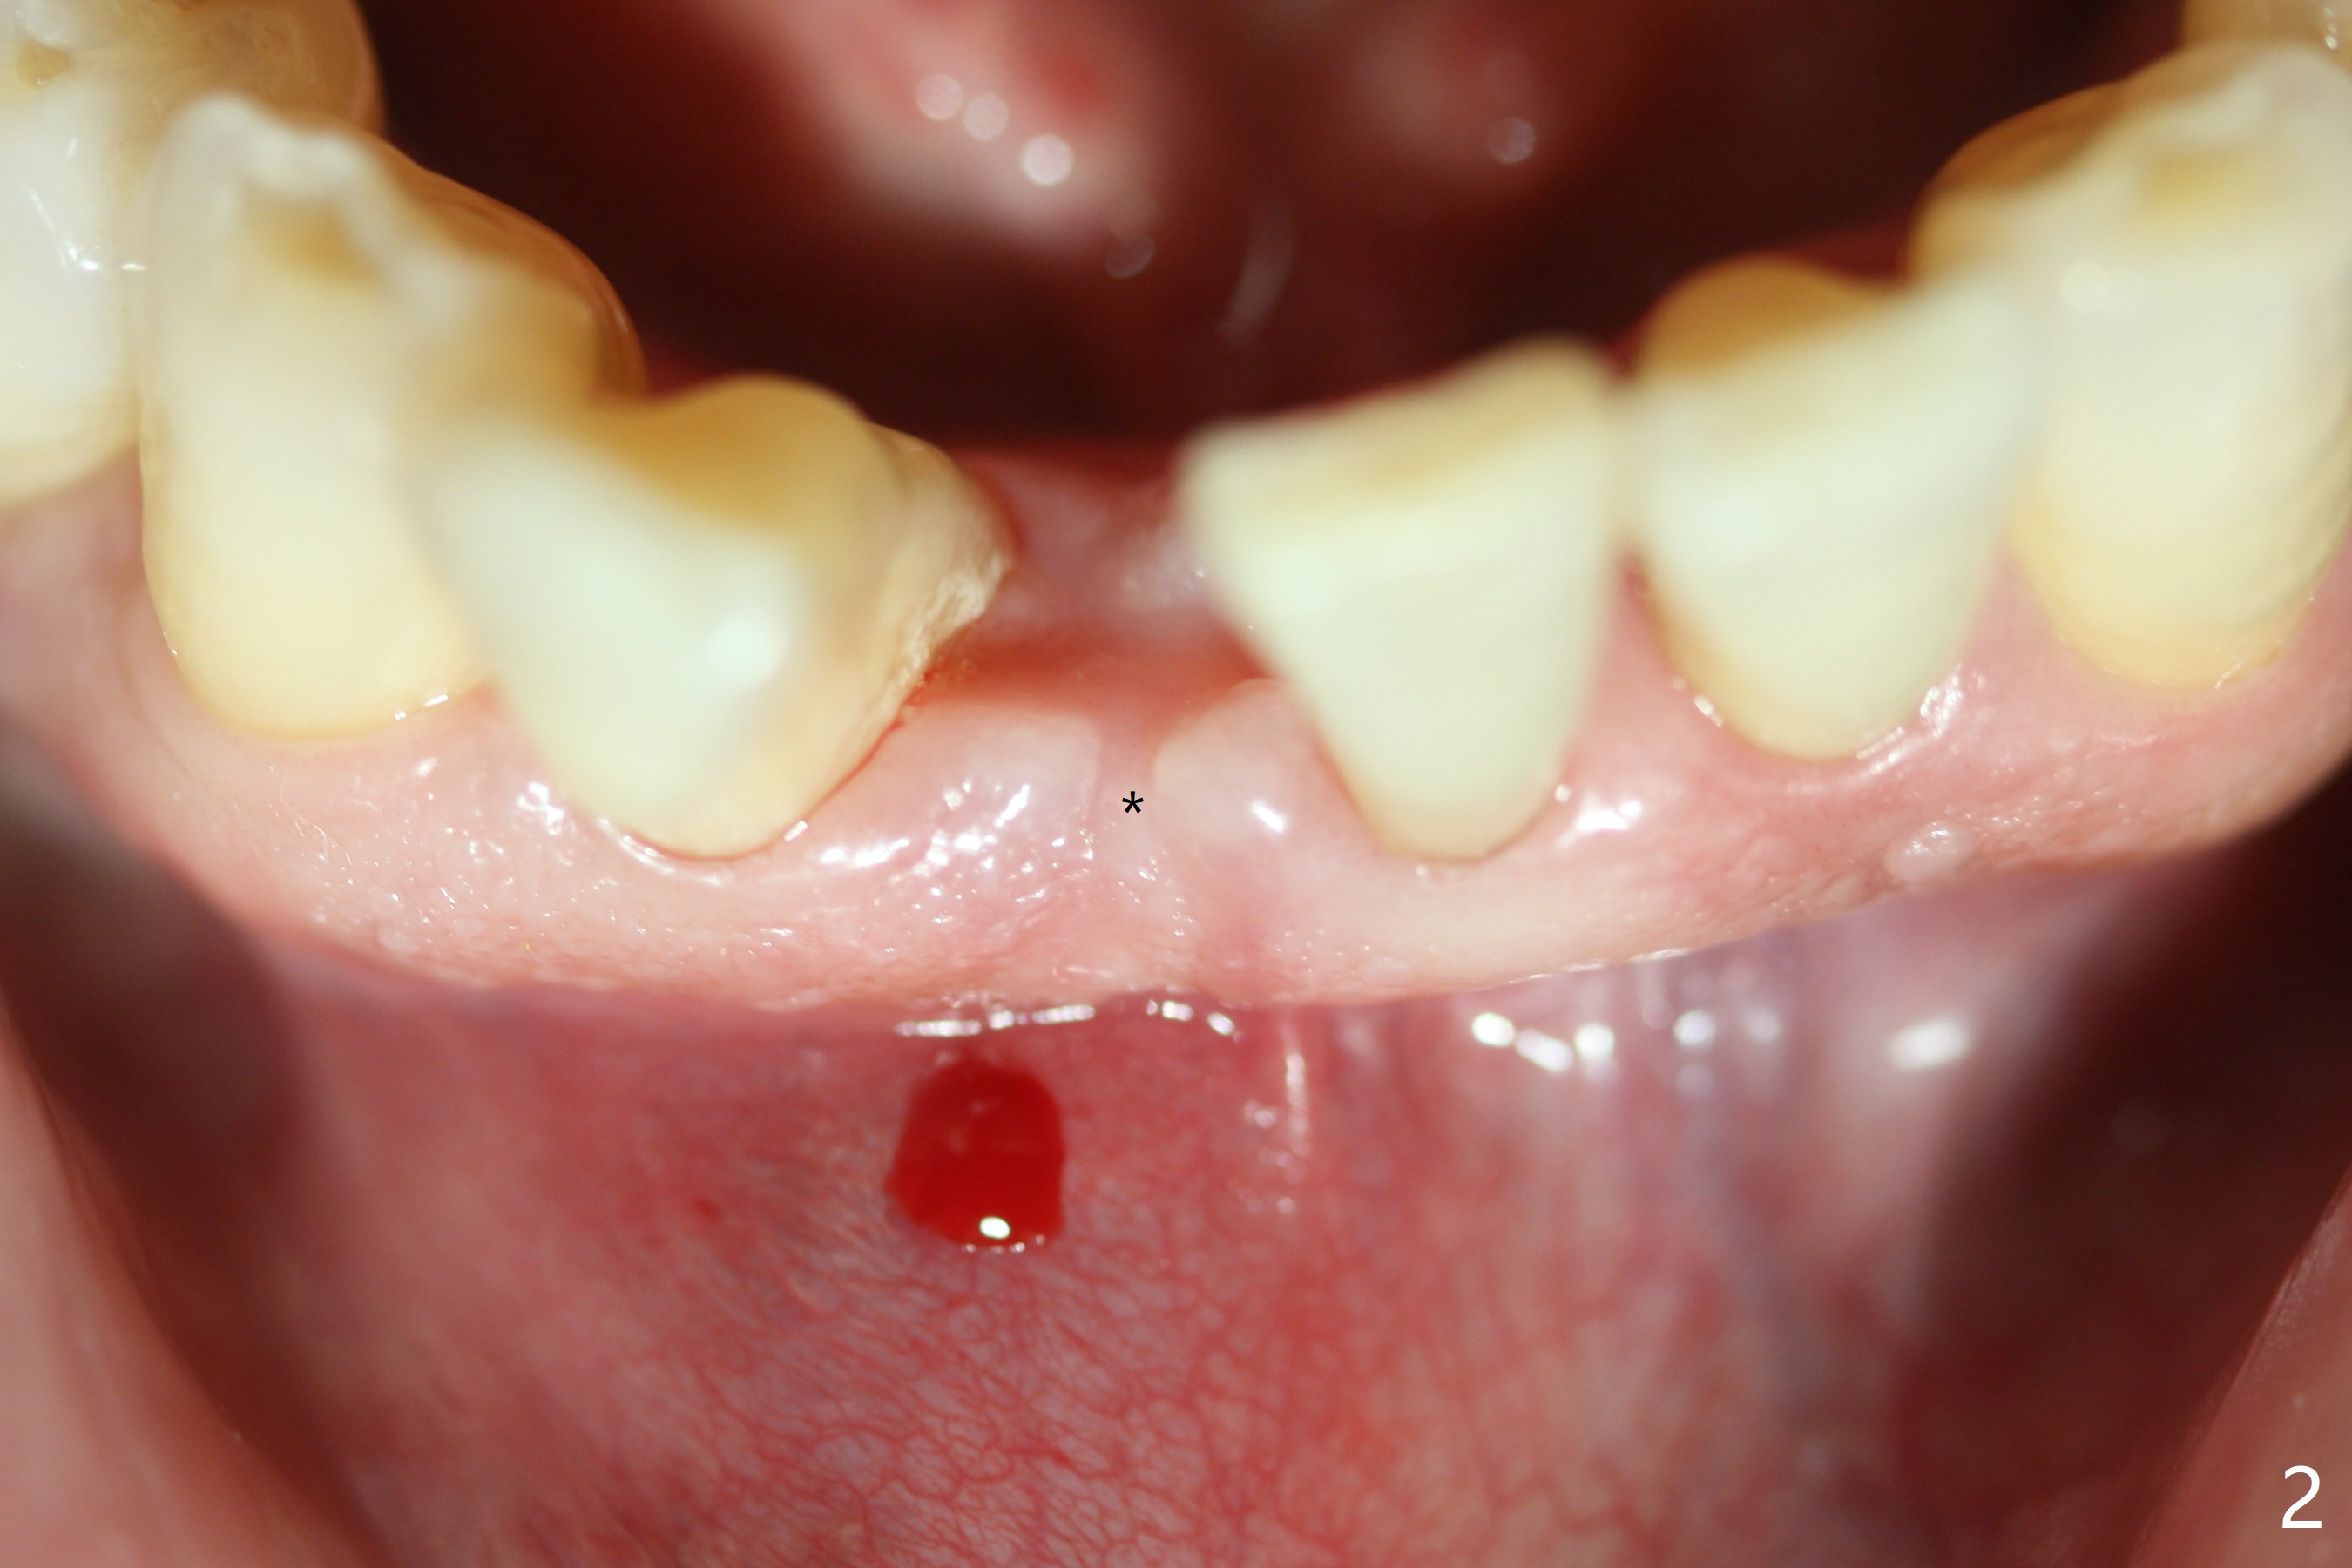

Implant

Out of financial concern, the patient does not agree to have the tooth #26 extracted. Due to atrophy of the most coronal ridge buccally at #25 (Fig.1,2 *), osteotomy is initiated difficult and distal (Fig.3). After 1.2 mm drill removal (Fig.3' black area), Lindamann bur is used to move the osteotomy mesial (red area). A 2x12(4) mm 1-piece implant is placed (Fig.4,5); the buccal defect is packed with allograft (Vanilla, .5-1 mm cancellous/cortical mixture, *). When the tooth #26 fails, a 2 mm implant will be placed (Fig.6 blue). Following abutment adjustment, a provisional is fabricated (Fig.7 P); note the lower incisal edges of #25 and 26, as compared to those of the neighboring teeth. To reduce occlusal trauma, the incisal edge of the tooth #26 has been decreased (Fig.5 open arrow). The implant threads seem not to be exposed 4 months postop (Fig.8), although the tooth #26 has mobility II.